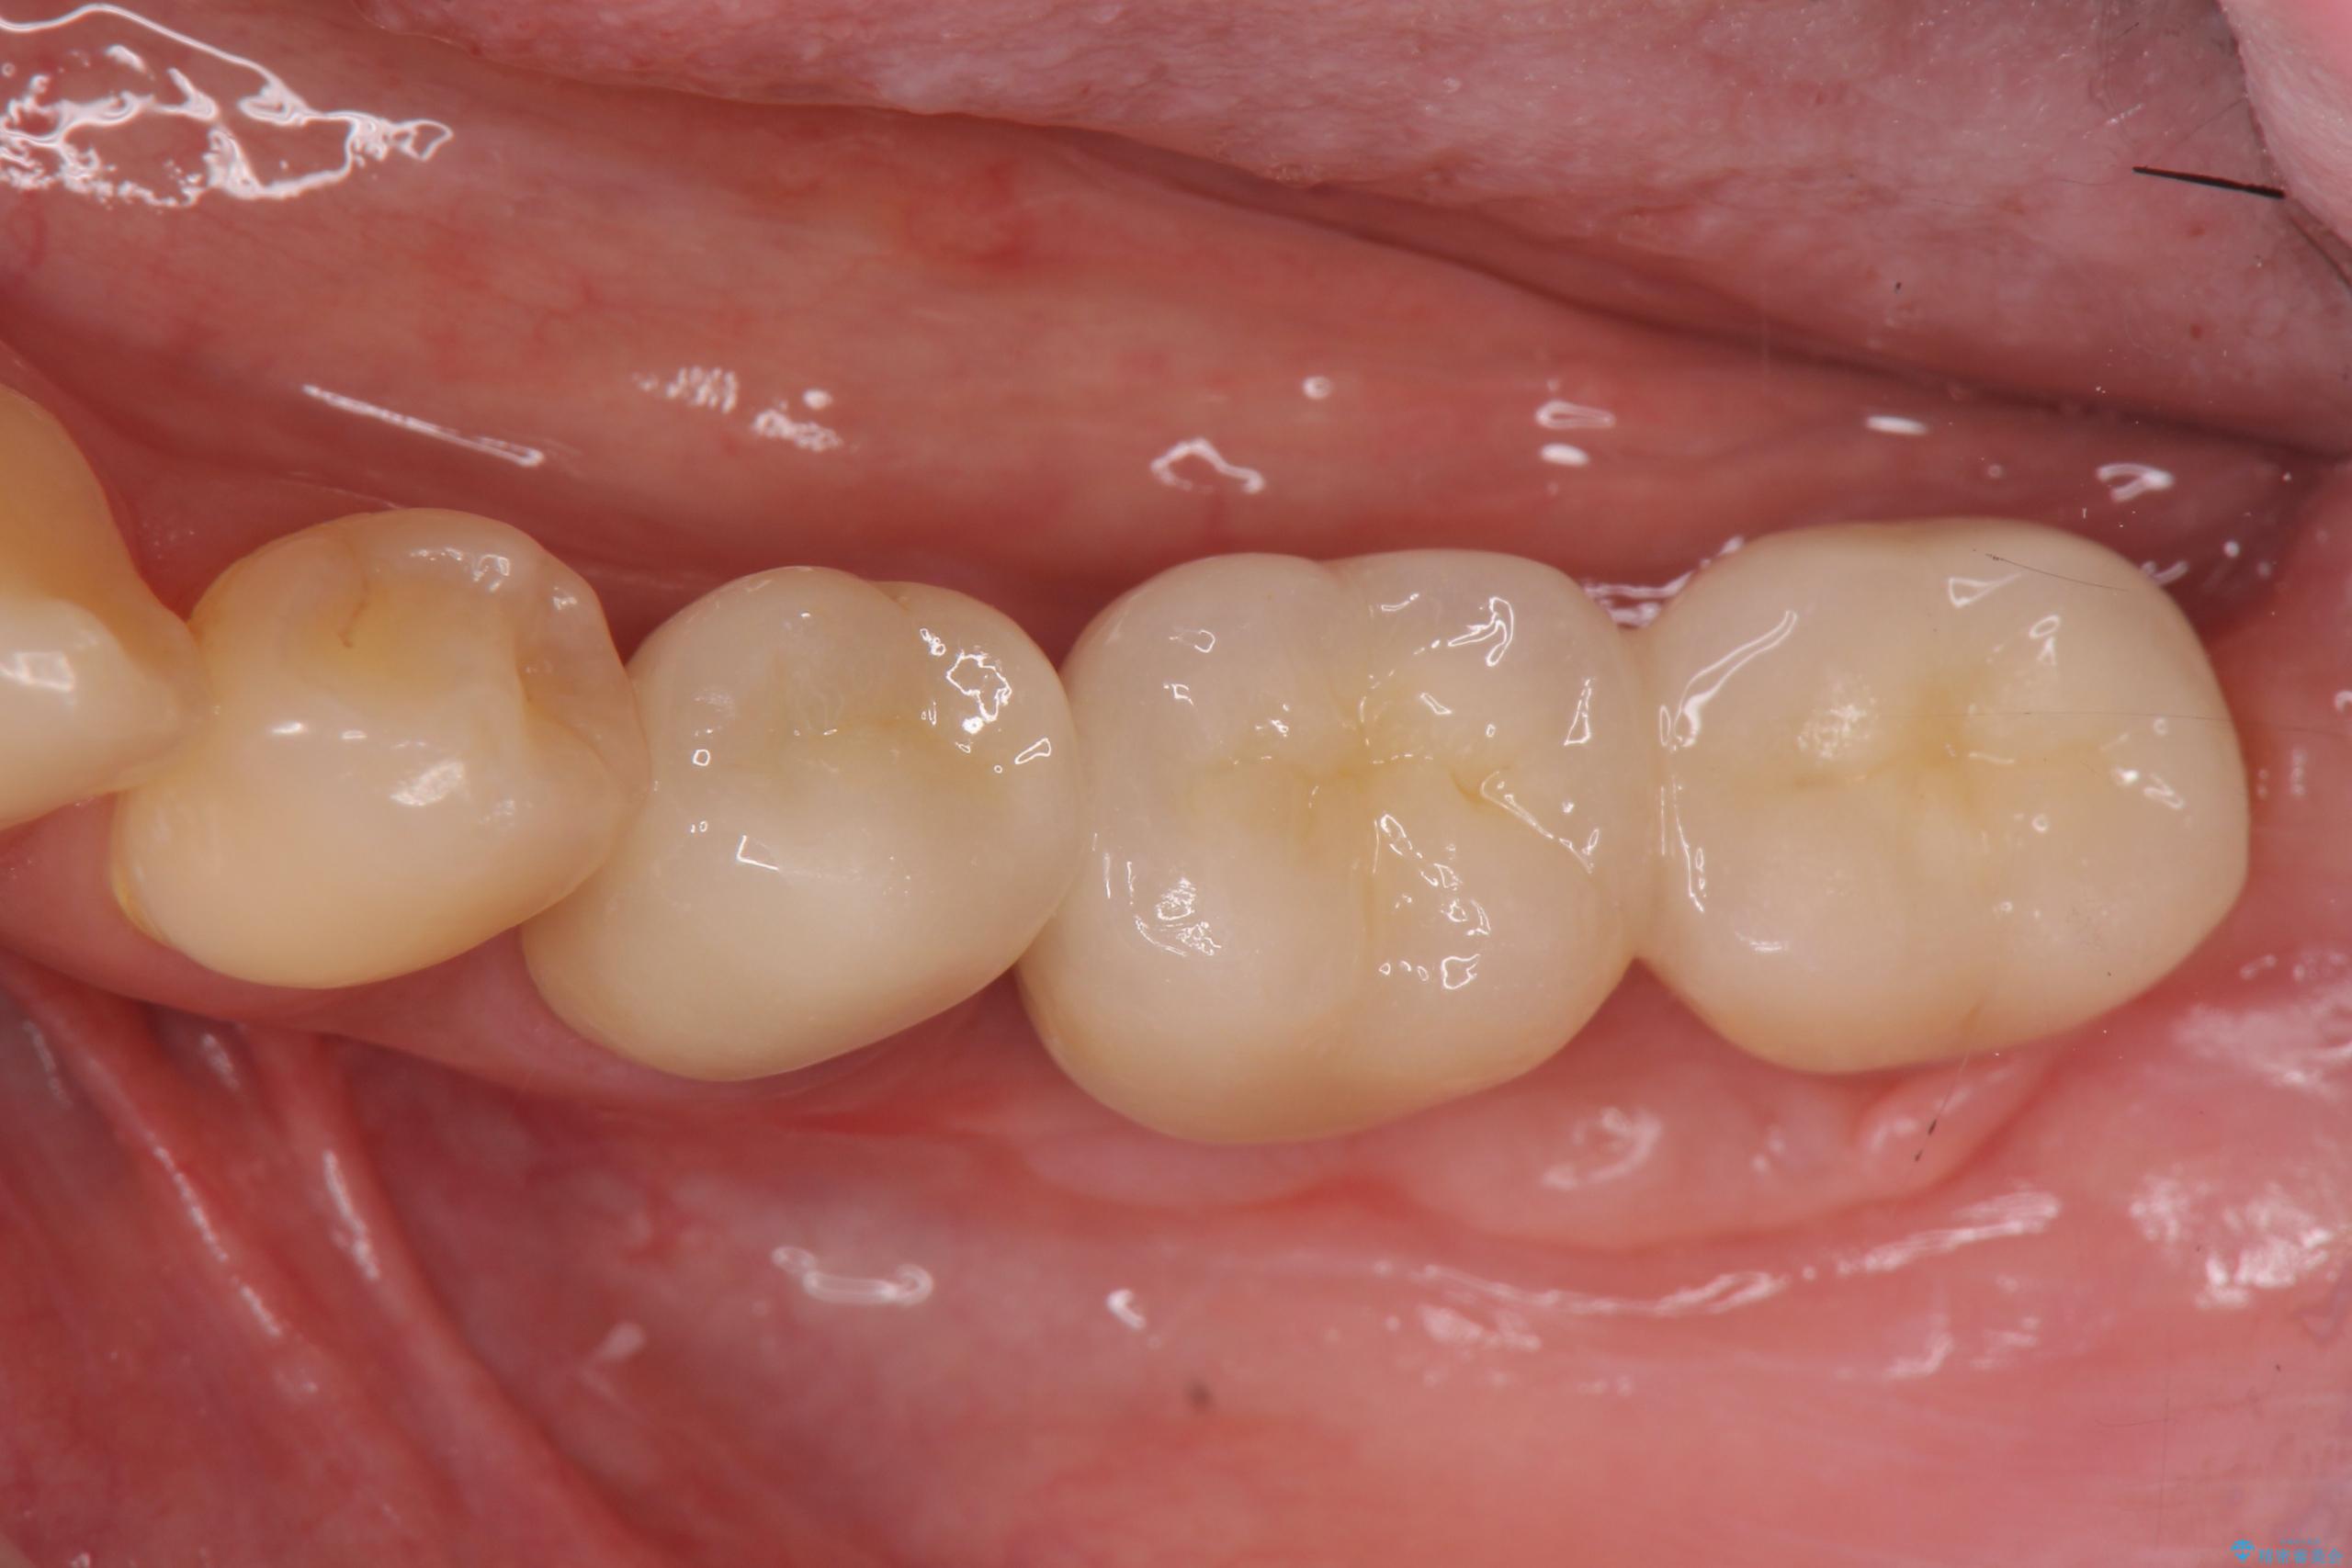

遊離歯肉移植術を併用した、破折歯のインプラント治療

- 83.6万円(インプラント×2・アバットメント×2・クラウン×2)費用は治療当時の料金となります

インプラント周囲の角化歯肉が存在することにより、歯ブラシがしやすくなりインプラントにトラブルが起きる確率を減らしより長期的な予後を望むことができます。